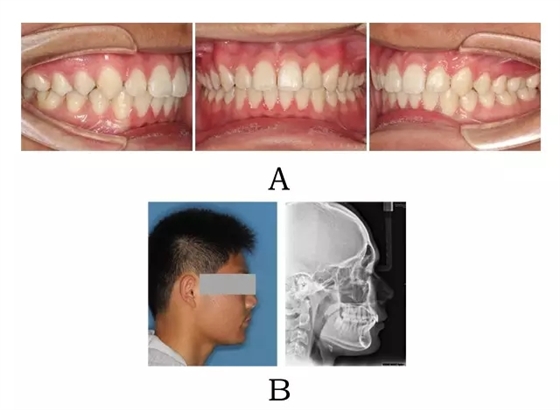

640.webp (3).jpg

圖4-3:混合I型突面畸形矯形治療臨床療效及頭顱側(cè)位影像變化。

(A) 咬合改善 (B) 側(cè)貌改變

Figure 4-3. Treatment outcomes for merged prognathism (Type I). (A) Occlusion correction. (B)Facial esthetic improvement.